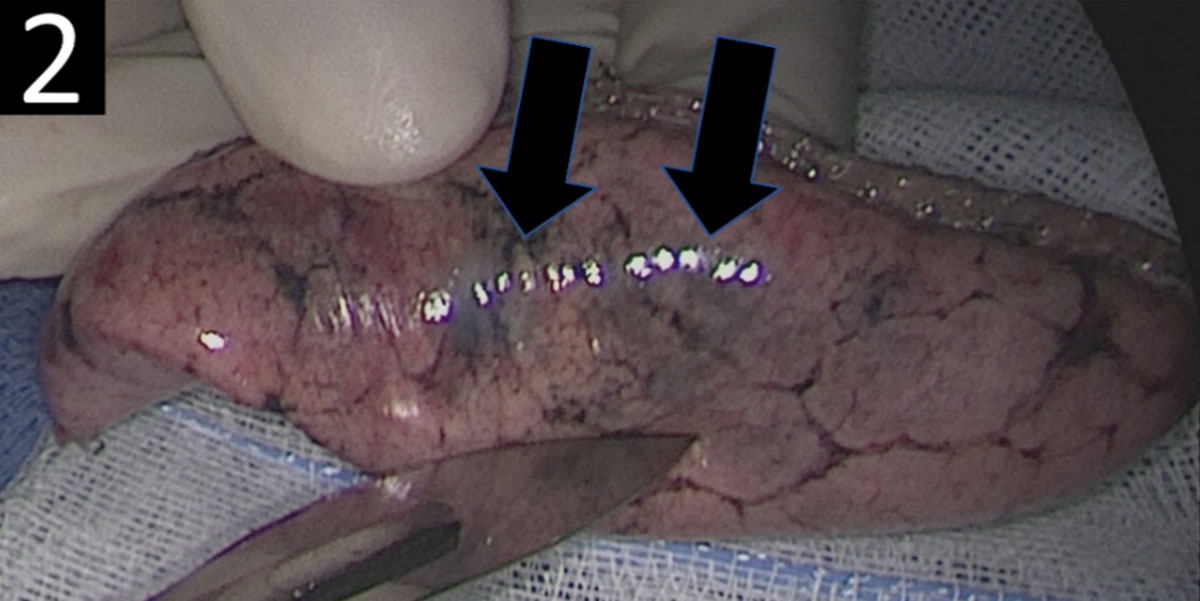

A lung biopsy of the right upper lobe was performed. Visual inspection of the specimen showed multiple bluish colored nodular lesions (Figure 2, black arrows).

Figure 2